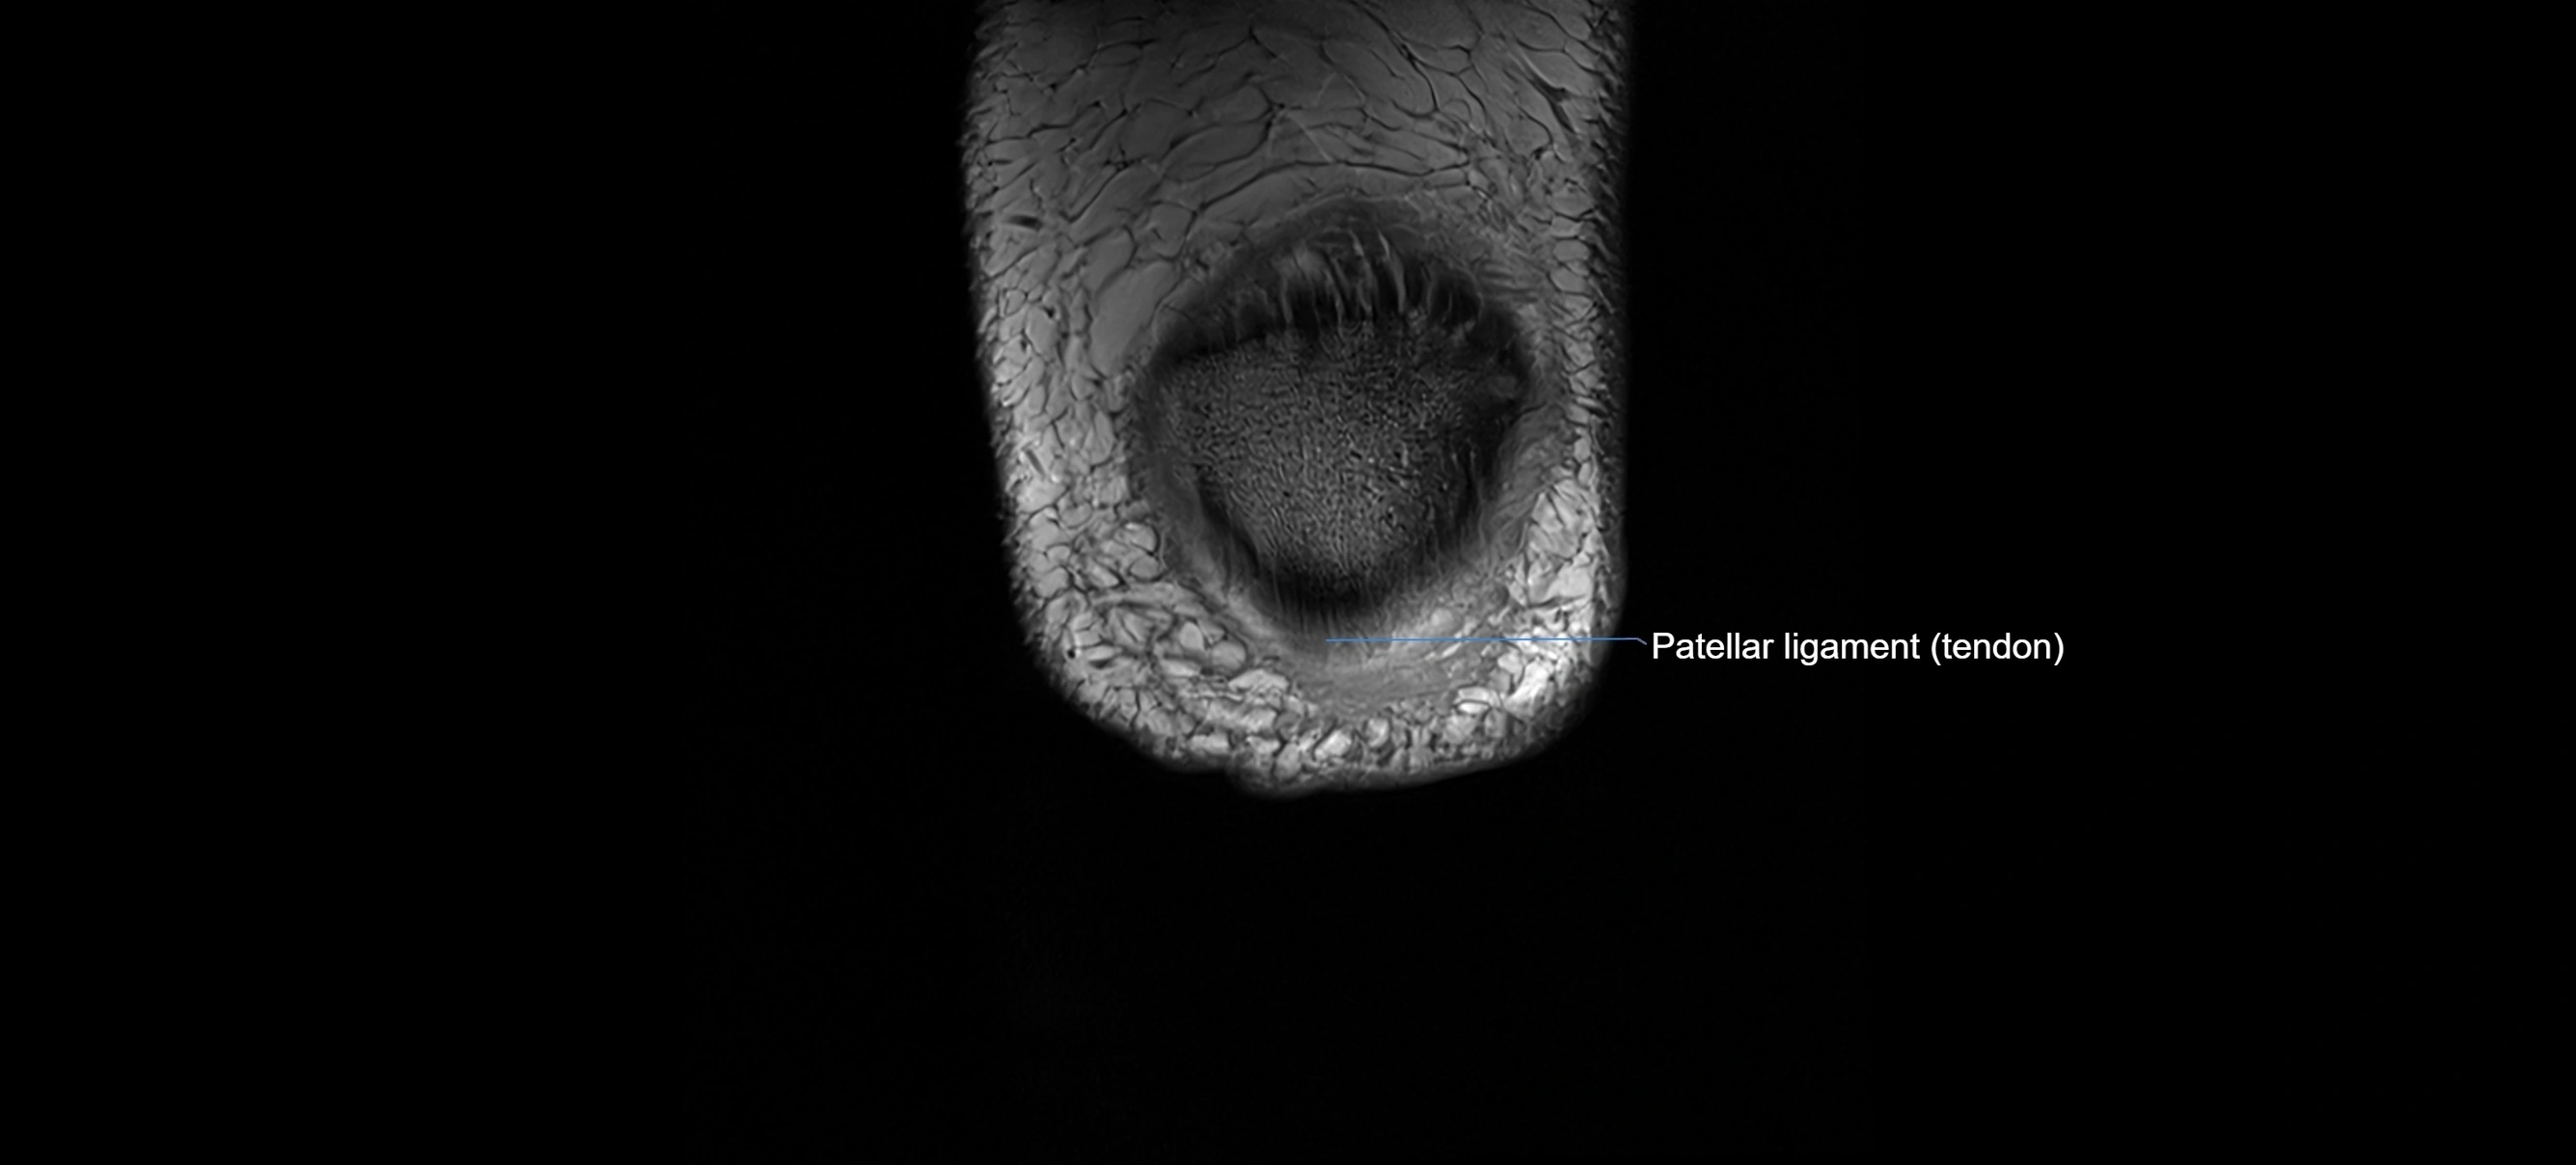

MRI images

image

MRI Appearance

Proton Density Fat-Saturated (PD FS):

• Normal ACL: dark, low-signal band

• Tears: bright intraligamentous hyperintensity, discontinuity, or abnormal course